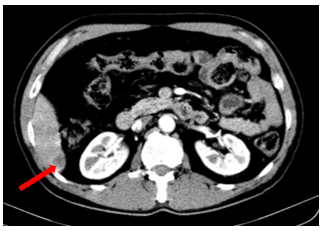

Hình 3.

Hình ảnh khối u gan (mũi tên)

Hình 5.

Hình ảnh phim chụp cắt lớp vi tính bụng ngày 10 tháng 7 năm 2025 (mũi tên trắng) so với ngày 19 tháng 03 năm 2025 (mũi tên đỏ) cho thấy hình ảnh khối u gan đã gần như biến mất hoàn toàn.